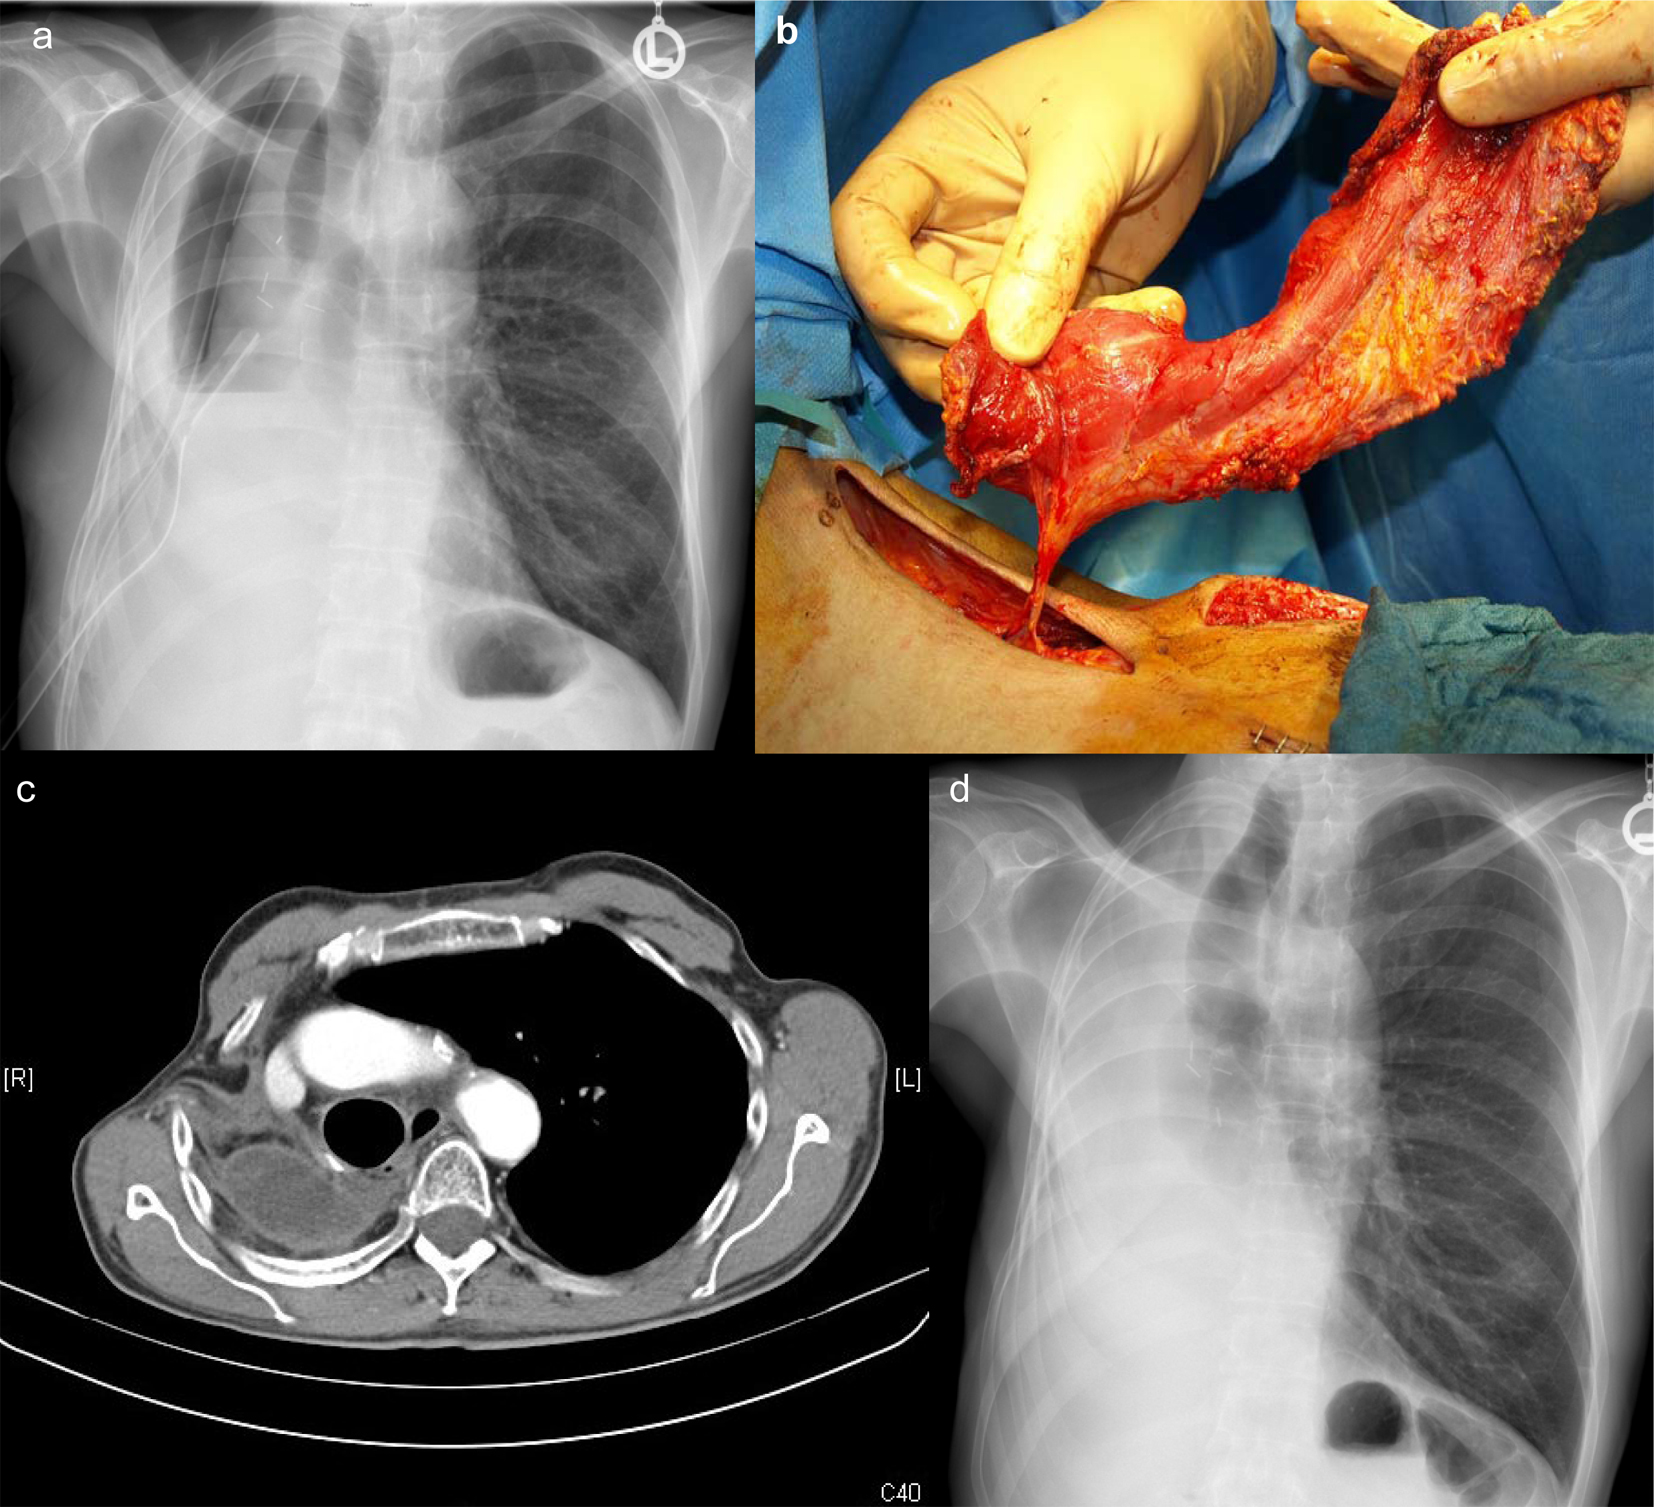

![]() Click for large image | Figure 1. Images demonstrating the progress of treatment: (a) X-ray of the chest demonstrating thickened right-sided thoracic wall and two drains, the day before open debridement; (b) preparation of the pedicled latissimus dorsi muscle flap; (c) CT-scan 3 months after definitive closure demonstrating adequate shift of the mediastinum to the right side and the entrance of the muscle; (d) corresponding chest X-ray after 3 months. |

IV vancomycin and intensive irrigation with normal saline did not eradicate MRSA, but allowed the patient to recover from severe septicemia. Filling the cavity with vancomycin solution was not effective either. The irrigation fluid remained cloudy and positive for MRSA (Fig. 1a). The open debridement demonstrated a thick peel formation with fibrin and pus attached all over the cavity. Two further debridements were necessary to gain adequate clearance before muscle coverage was possible (Fig. 1b). The patient tolerated all operative procedures and recovered, gained weight and was fully mobilized. He was discharged 17 days after the latissimus myoplasty. The pleural fluid aspirate 3 weeks and also 3 months later as well as the nose swabs and sputum were negative for MRSA, and the patient was free of inflammatory signs. Computed tomography of the thorax demonstrated no abscess formation and no signs of tumor recurrence at 3 months (Fig. 1c, d).